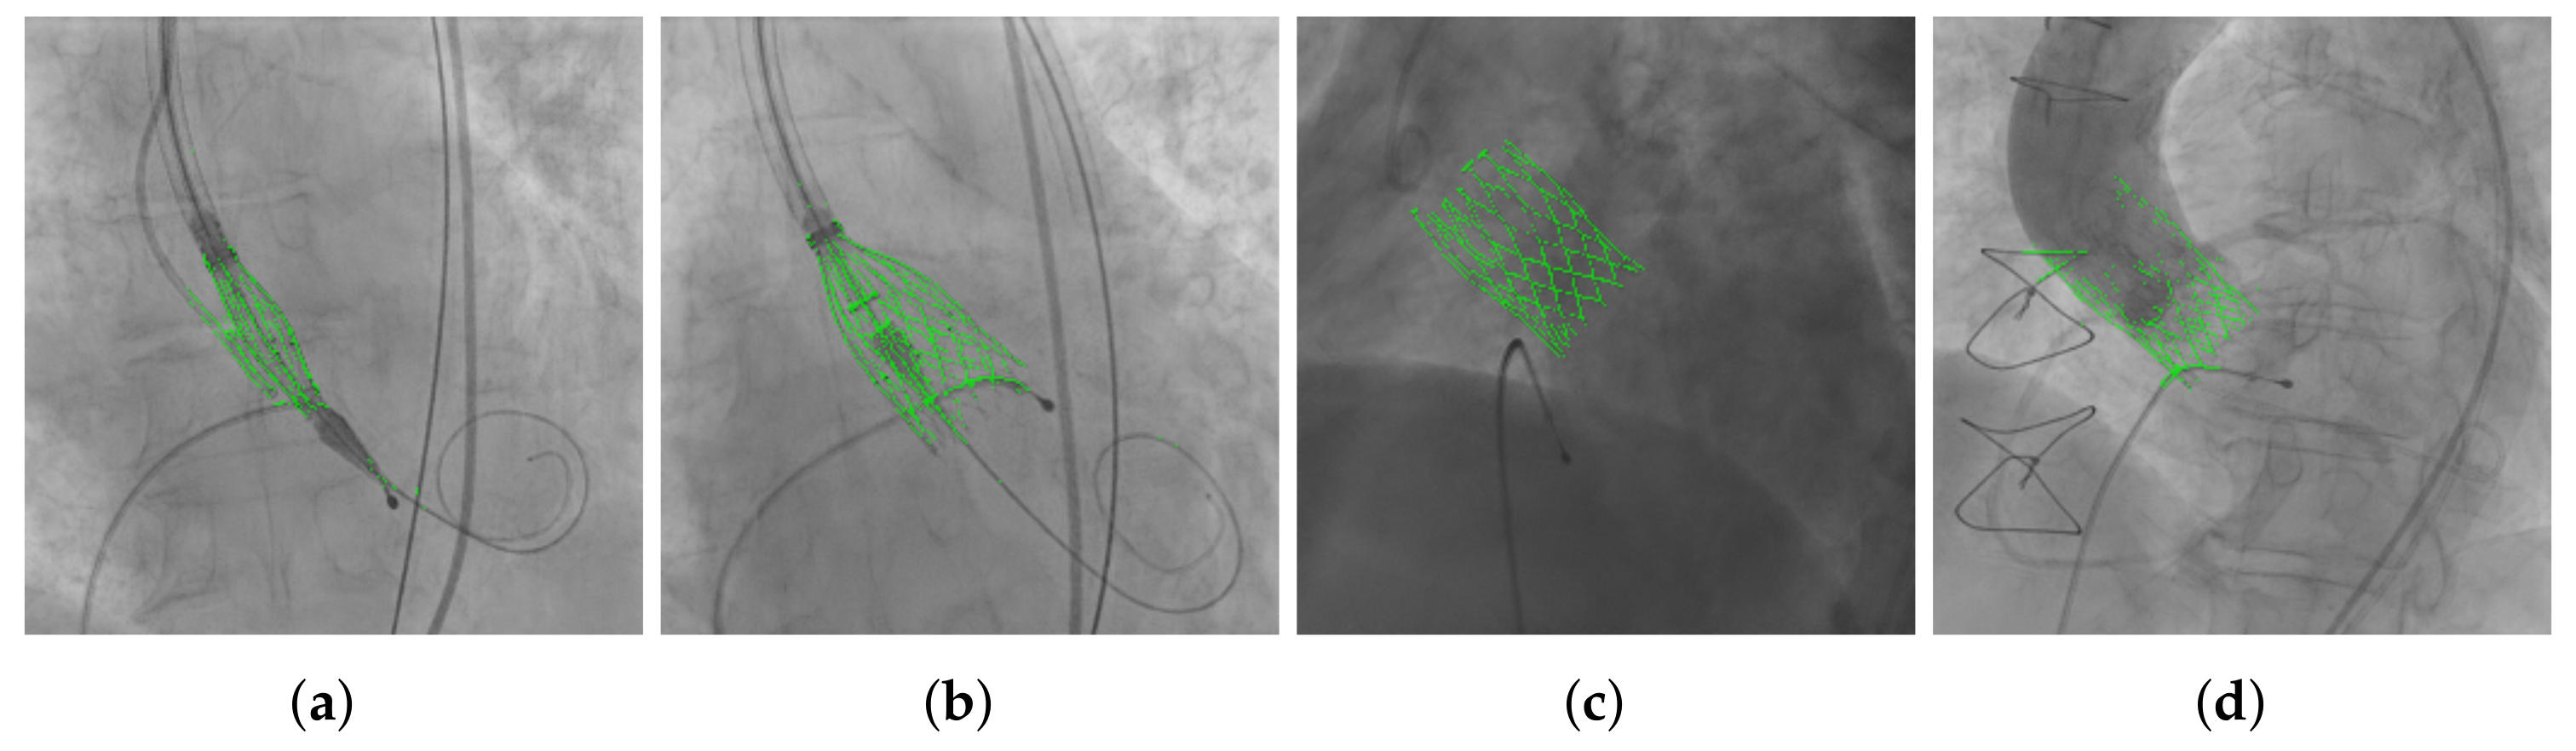

3.3. THV Segmentation